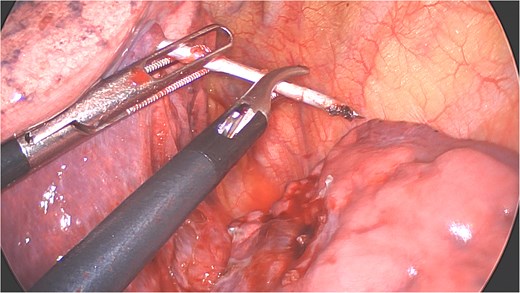

A clear minor pleural effusion and translucent scissural and para-aortic adhesions were visible. The adhesions of the pulmonary apex were released but no abnormality of the parietal pleura nor bone was visible. As the lung then collapsed, the pin became spontaneously visible protruding in the main fissure. As expected, the proximal part was in segment 2 and the distal half inside the apical segment of the lower lobe (S6) but it did not protrude outside of the parenchyma on either side (Fig. 4). The K-wire was easily removed by gently pushing back the parenchyma towards both extremities (Fig. 5). The pin seemed to be surrounded by a fine membrane that was coagulated at the visceral pleural entry point.

Distal part of K-wire stuck in segment 2 and the proximal part in the apical segment 6.